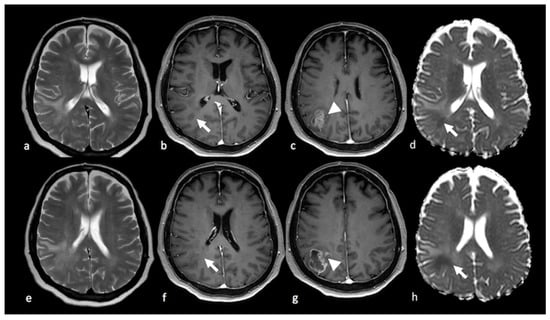

3.1. Conventional MRI

- Tang, Y.M.; Ngai, S.; Stuckey, S. The solitary enhancing cerebral lesion: Can FLAIR aid the differentiation between glioma and metastasis? AJNR Am. J. Neuroradiol. 2006, 27, 609–611. [Google Scholar] [PubMed]

- Wang, P.; Shi, Y.H.; Li, J.Y.; Zhang, C.Z. Differentiating Glioblastoma from Primary Central Nervous System Lymphoma: The Value of Shaping and Nonenhancing Peritumoral Hyperintense Gyral Lesion on FLAIR Imaging. World Neurosurg. 2021, 149, e696–e704. [Google Scholar] [CrossRef]